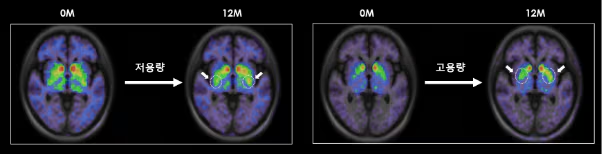

低劑量和高劑量TED-A9植入一年后的腦成像。

尤其是在干細胞治療帕金森病植入一年后,對腦成像圖像進(jìn)行分析后發(fā)現,多巴胺轉運蛋白的表達較植入前有所增加。干細胞治療的開(kāi)發(fā)者、延世大學(xué)醫學(xué)院金東旭教授指出:“這表明干細胞在腦內存活,成熟為多巴胺神經(jīng)細胞,并與周?chē)鷧^域和突觸(神經(jīng)細胞之間的連接)形成整合?!彼a充道:“這可以被視為帕金森病中替換死亡多巴胺神經(jīng)細胞的根本治療機制的有力證據?!?/p>